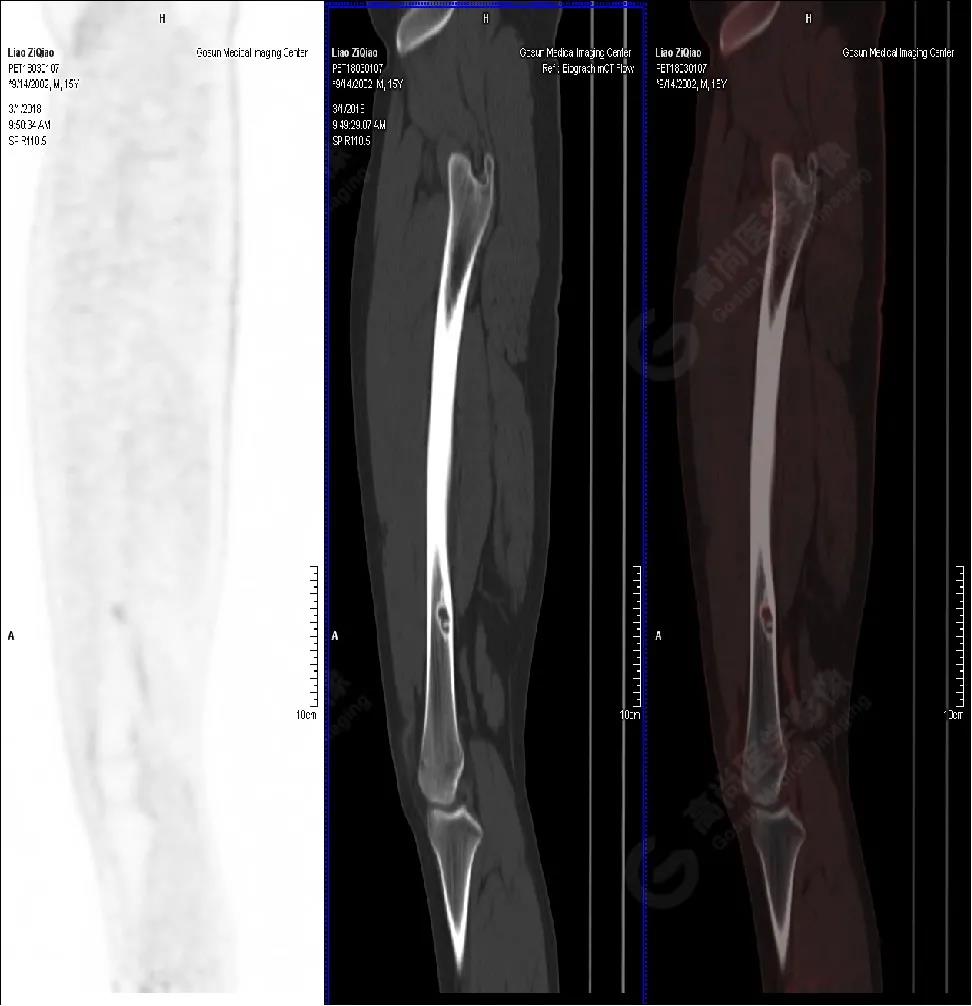

男性,15歲,右側(cè)大腿疼痛1月余,DR提示右側(cè)股骨下段囊性低密度占位。既往無外傷史、否認(rèn)肝炎、結(jié)核及手術(shù)史。

PET/CT檢查

PET/CT表現(xiàn)

右側(cè)股骨下段(內(nèi)側(cè)緣)見骨皮質(zhì)局限性膨脹性破壞,突入髓腔內(nèi),邊界清楚,邊緣硬化,灶內(nèi)見纖維骨嵴,放射性攝取略增高,SUV最大值為1.4,平均值為1.3。

PET/CT診斷

右側(cè)脛骨良性骨病,以非骨化性纖維瘤可能性大。

病理診斷

隨訪結(jié)果:活檢病理確診非骨化性纖維瘤。